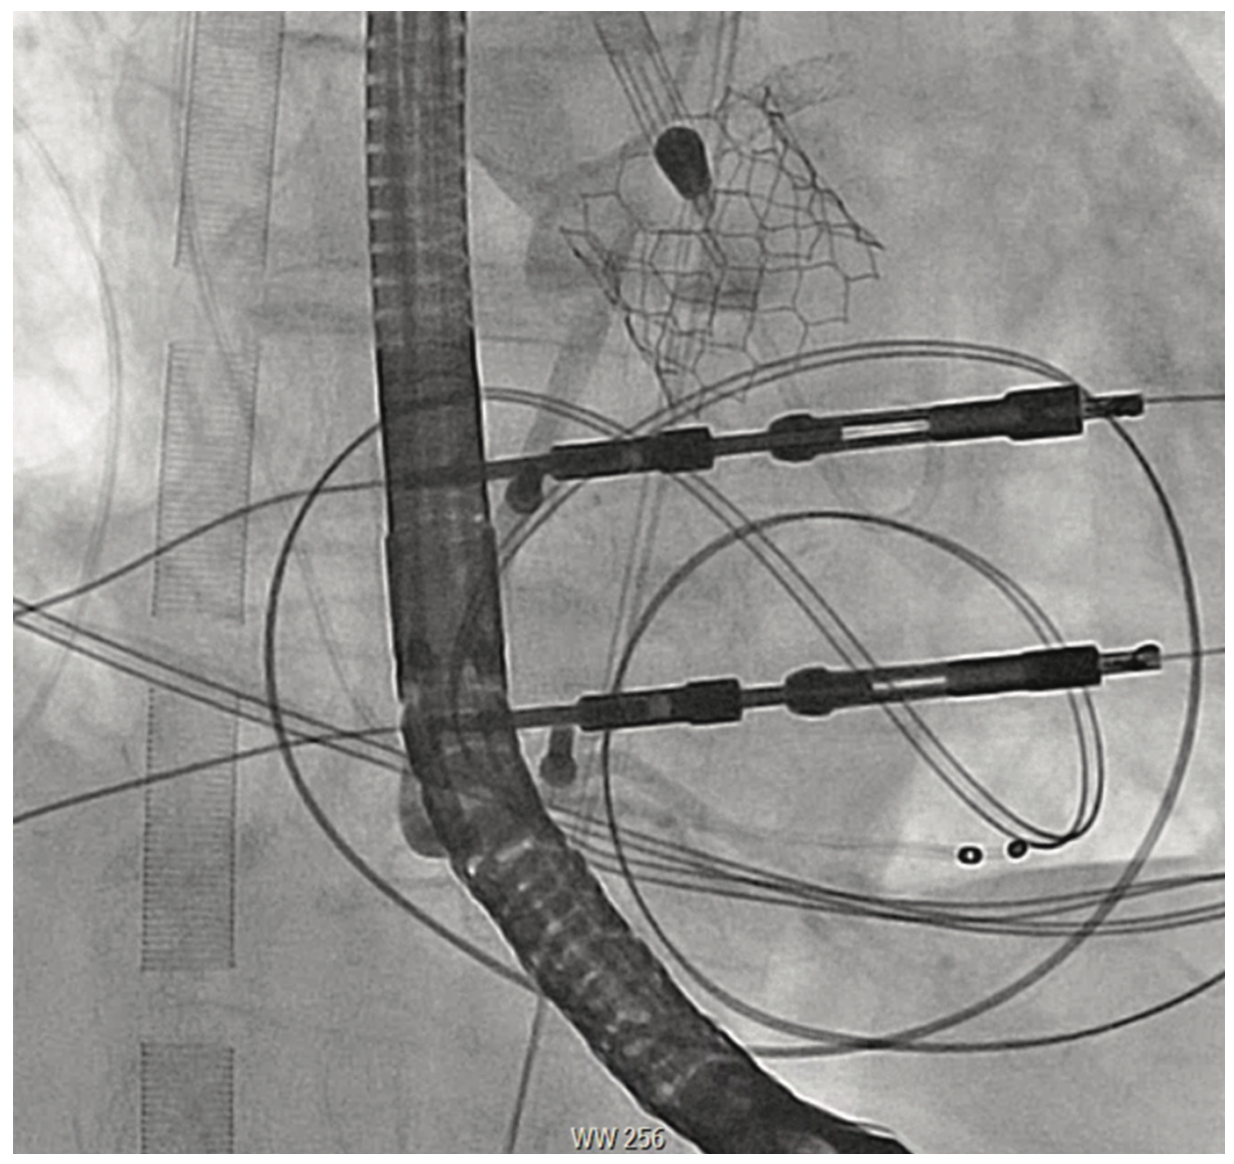

An 81-year-old female with symptomatic severe aortic stenosis, logistic EuroSCORE I (European System for Cardiac Operative Risk Evaluation) of 14.46%, EuroSCORE II of 3.44%, and Society of Thoracic Surgeons (STS) estimated surgical mortality of 3.371%, underwent TAVR. Transthoracic echocardiogram (TTE) showed a heavily calcified aortic valve with a mean gradient of 68 mmHg, aortic valve maximum velocity (Vmax) of 4.2 m/sec, calculated aortic valve area of 0.8 cm2, and normal left ventricular systolic function. Computed tomography angiography (CTA) demonstrated heavily calcified aortic root, leaflets, and annulus. Transfemoral implantation of a 23 mm Sapien 3 (Edwards Lifesciences) valve was performed (Figures 1-2). Using a 20 mm balloon for pre-dilation, the valve was implanted successfully in a 50-50 position (Figure 3). The immediate post-deployment aortogram showed leakage of dye outside the left sinus with no evidence of cardiac tamponade. Despite that fact, the patient developed immediate hemodynamic collapse. QRS widening and ST-elevation were visible on the monitor. Narrowing of the left main coronary artery (LMCA) with reduced TIMI flow (0-1) was evident in angiographic images (Figures 4-5). The patient had a cardiac arrest, cardiopulmonary resuscitation was initiated, and she went into cardiogenic shock. The patient stabilized with the placement of venoarterial extracorporeal membrane oxygenation (VA-ECMO) and the insertion of the Impella device (Abiomed) (Figure 6). An emergent percutaneous intervention was performed within minutes from collapse by the deployment of two drug-eluting stents from the LMCA into the left anterior descending (LAD) coronary artery (Figure 7) using the Culotte technique with final kissing-balloon dilatation. After the restoration of coronary flow, the patient was admitted to the cardiothoracic intensive care unit. She remained stable. The ECMO and Impella implant was removed after 7 days. Postprocedure on day 14, the patient was discharged to a rehabilitation facility. Echocardiography showed a well-functioning valve with acceptable residual gradient and mild to moderate paravalvular leak.